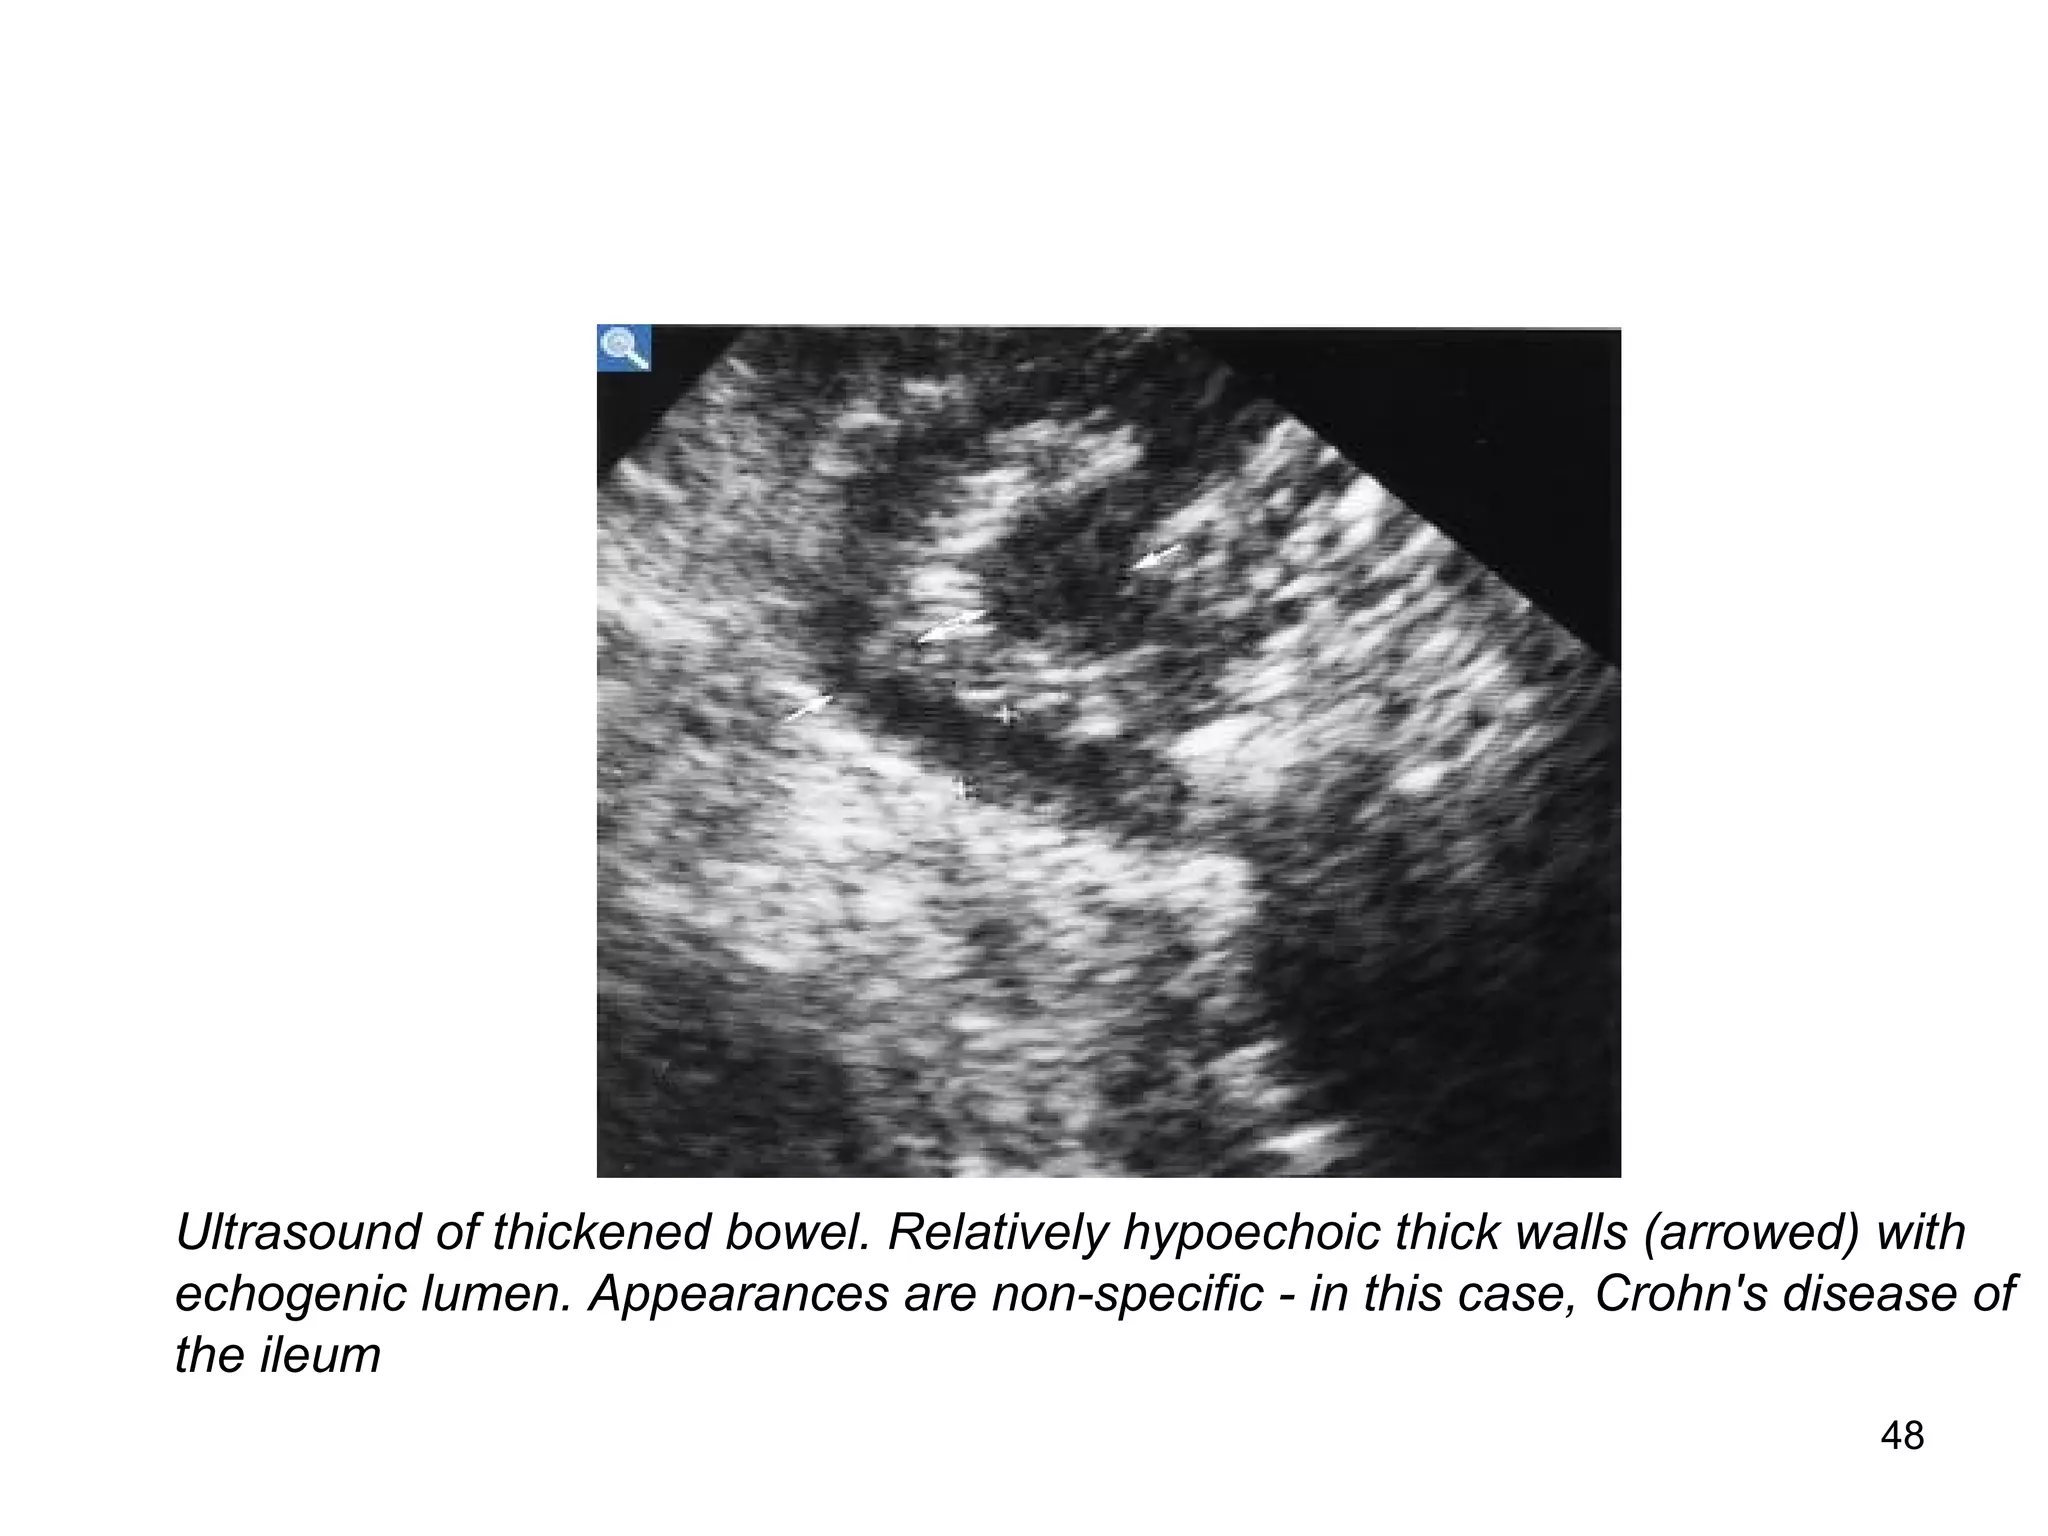

Ultrasound of thickened bowel. Relatively hypoechoic thick walls (arrowed) with

echogenic lumen. Appearances are non-specific - in this case, Crohn's disease of

the ileum

48 Ultrasound of thickenedbowel. Relatively hypoechoic thick walls (arrowed) with echogenic lumen. Appearances are non-specific - in this case, Crohn's disease of the ileum